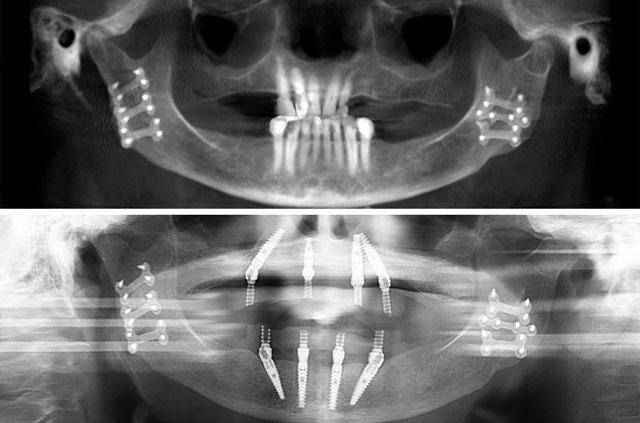

What is the All-on-4 Technique?

All-on-4 is a revolutionary dental implant technique that uses just four strategically placed implants to support a full arch of replacement teeth. The posterior implants are angled at 30-45 degrees to maximize bone contact and avoid anatomical structures like the maxillary sinus or inferior alveolar nerve. This innovative approach allows for immediate loading with a temporary prosthesis, providing same-day teeth and eliminating the need for lengthy healing periods between procedures.